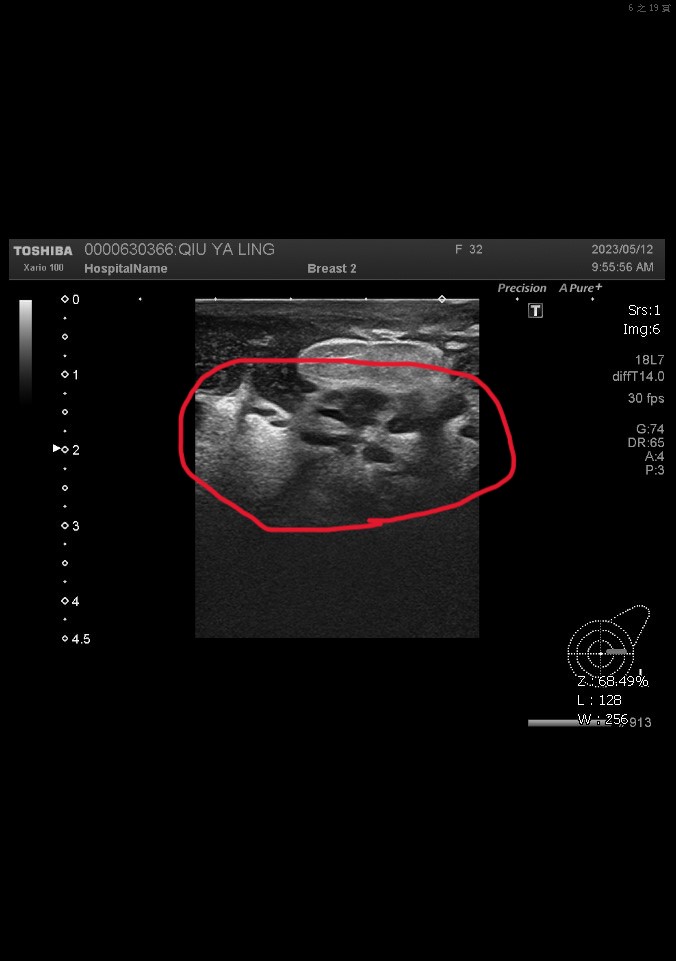

▲33歲患者乳房因結核菌感染導致組織壞死,之後接受手術切除壞死組織並接受抗結核病藥物治療。

(員榮醫院提供)

這名患者4月間左側乳房腫痛,且摸到硬塊、紅腫及疼痛,先到某診所求醫,服用抗生素一個月仍未好轉,林女十分憂心乳房不保,5月間到員榮求診。陳國棟醫師為林女進行乳房超音波檢查,發現已有部分組織壞死,先手術切除壞死組織,將膿瘍引流出來,再給予抗生素控制,並進行細菌培養。